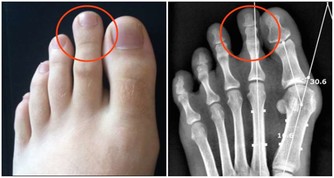

肥肉生濕生痰,還會加重脾虛和肺熱的症狀,在孩子感冒期間我們的飲食應該有所調整,不能再像平日里那麼多大魚大肉,這樣不但不會讓咳嗽痊癒,還會一直拖一直拖,咳嗽拖成支氣管炎就更難治癒了。